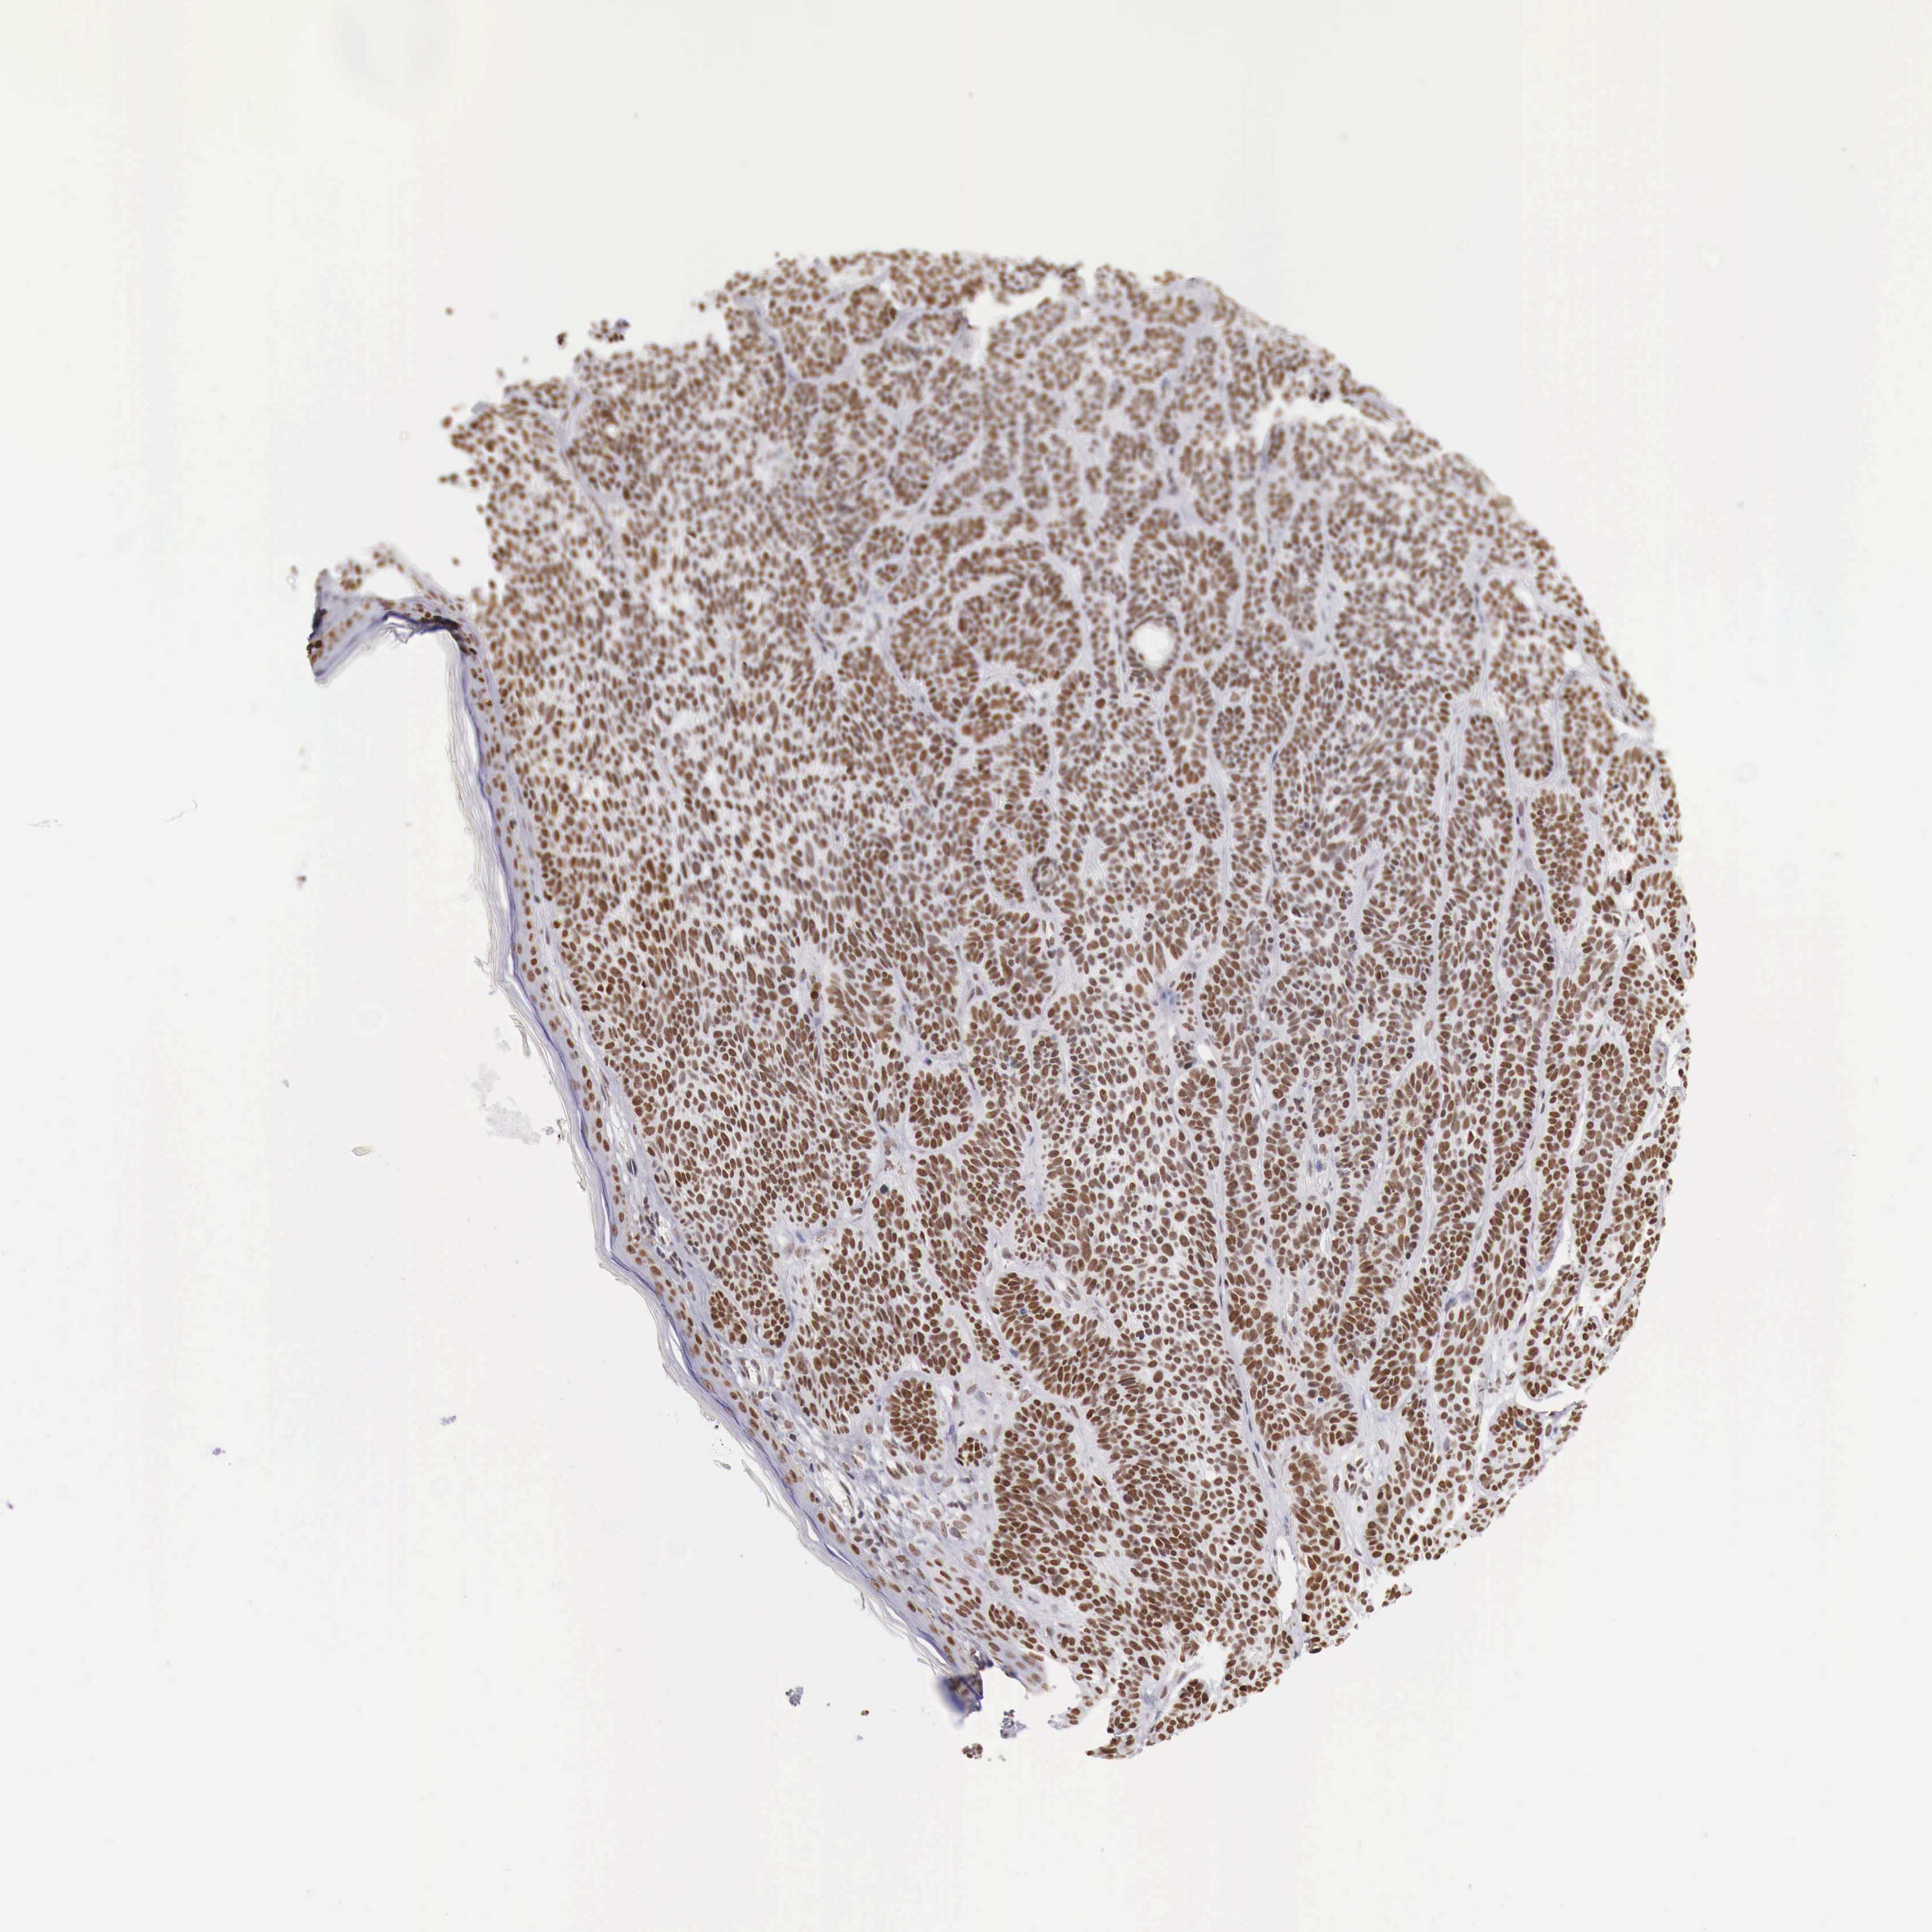

SKIN CANCER - Protein expressioni

A mouse-over function shows sample information and annotation data. Click on an image to view it in a full screen mode. Samples can be filtered based on level of antibody staining by selecting one or several of the following categories: high, medium, low and not detected. The assay and annotation is described here.

Antibody staining in the annotated cell types in the current human tissue is reported as not detected, low, medium, or high, based on conventional immunohistochemistry profiling in selected tissues. This score is based on the combination of the staining intensity and fraction of stained cells.

Each image is clickable and will lead to virtual microscopy that enables deeper exploration of all samples and also displays staining intensity scores, fraction scores and subcellular localization as well as patient and tissue information for each sample.

Antibody HPA000538

Staining

High

Intensity

Strong

Quantity

>75%

Location

Nuclear

Squamous cell carcinoma, NOS